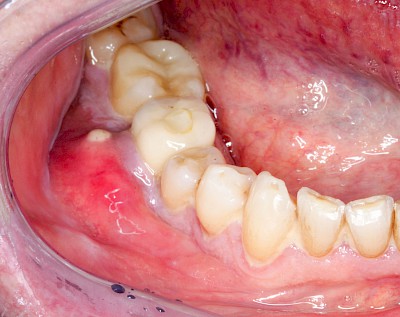

Schwellung ohne Eiter: kugelförmig

Demgegenüber entstehen Auftreibungen der Weichgewebe in Folge mechanischer Dauerreize (Reizfibrom) langsam über Wochen, Monate oder Jahre. Auch Gewohnheiten (Wangensaugen, Lippenbeißen) mit geringem Druck können als Dauerreiz in der Folge zu einer Wucherung der Weichgewebe führen. Fibrome werden nicht selten auch beobachtet in der Nähe einzelner fehlender Zähne – die Lippen oder Wangen beginnen dann, diesen Raum "aufzufüllen" (Vakatwucherung). Reizfibrome sind meist "kugelartig".